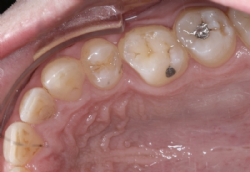

- Erschwerte Mundhygiene

Durch geeignete Putztechnik (spezielle Bürstchen) ist die Reinigung der Zähne trotzdem sehr gut möglich; das Gerät selbst schädigt den Zahnschmelz nicht und: ein sauberer Zahn wird nicht von Karies befallen! - Irritation der Mundschleimhaut zu Beginn der Behandlung